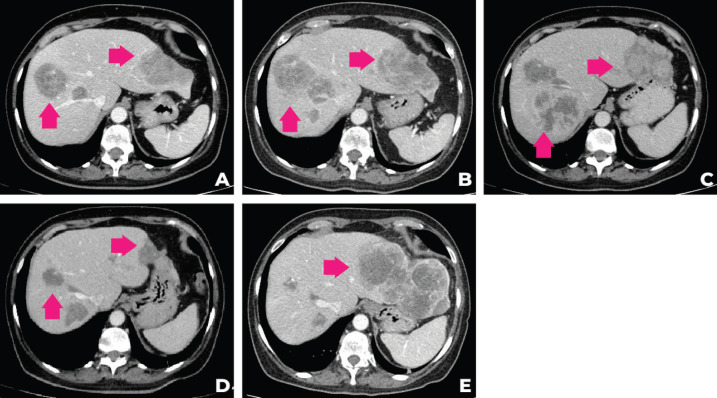

考慮到患者的臨床病程和多基因檢測包的結(jié)果,MTB 第二次會議討論建議進行腫瘤靶向藥物基因檢測850的遺傳咨詢,并開始使用他拉唑帕尼進行全身治療。 遺傳咨詢后,進行了 33 個基因組,包括與結(jié)腸癌、婦科癌和結(jié)直腸癌相關(guān)的基因(APC、ATM、AXIN2、BARD1、BMPR1A、BRCA1、BRCA2、BRIP1、 CDH1、CHEK2、DICER1、EPCAM、GREM1、MLH1、MSH2、MSH3、MSH6、MUTYH、NBN、NF1、NTHL1、PALB2、PMS2、POLD1、POLE、PTEN、RAD50、RAD51C、RAD51D、SMAD4、SMARCA4、STK11、TP53)的基因檢測。在所有檢測的基因中沒有任何一個被發(fā)現(xiàn)任何相關(guān)的突變或變異。 2021 年 9 月,經(jīng)過 talazoparib 治療 3 個月后,觀察到腹痛和肝臟部分反應(yīng)的臨床改善。 在提交本病例時(2021 年 12 月),腫瘤反應(yīng)正在進行中。 圖 2 描繪了患者主要放射學(xué)發(fā)現(xiàn)的總結(jié),圖 3 描繪了患者演變的時間表。

圖 2:患者計算機斷層掃描在不同時間段的演變。 (a):2020 年 12 月的 CT,(b):2021 年 4 月,(c):2021 年 6 月,(d):2021 年 9 月,(e):2021 年 12 月